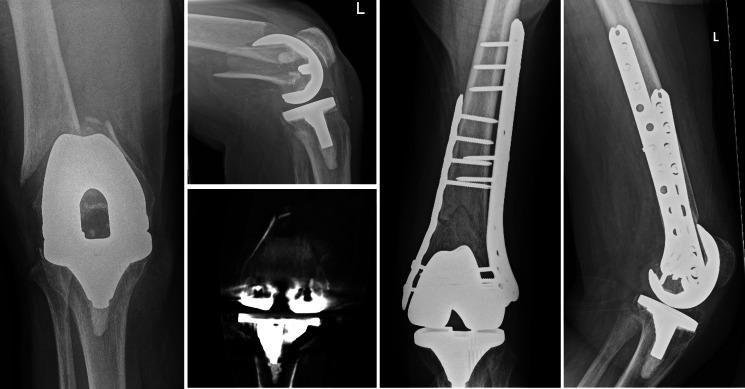

与单钢板固定和股骨远端关节成形术相比,双钢板固定是治疗人工关节周围股骨远端骨折的一种合适选择。

Double plating is a suitable option for periprosthetic distal femur fracture compared to single plate fixation and distal femoral arthroplasty.

The purpose of this study was to compare reoperation and revision rates of double plating (DP), single plating using a lateral locking plate (SP), or distal femoral arthroplasty (DFA) for the treatment of periprosthetic distal femur fractures (PDFFs).

A total of 111 PDFFs (111 patients, median age 82 years (interquartile range (IQR) 75 to 88), 86% female) with 32 (29%) Su classification 1, 37 (34%) Su 2, and 40 (37%) Su 3 fractures were included. The median follow-up was 2.5 years (IQR 1.2 to 5.0). DP, SP, and DFA were used in 15, 66, and 30 patients, respectively. Compared to SP, patients treated with DP were more likely to have metaphyseal comminution (47% vs 14%; p = 0.009), to be low fractures (47% vs 11%; p = 0.009), and to be anatomically reduced (100% vs 71%; p = 0.030). Patients selected for DFA displayed comparable amounts of medial/metaphyseal comminution as those who underwent DP. At a minimum follow-up of two years, revision surgery for failure was performed in 11 (9.9%) cases at a median of five months (IQR 2 to 9): 0 DP patients (0%), 9 SP (14%), and 2 DFA (6.7%) (p = 0.249).

CONCLUSION

Using a strategy of DP fixation in fractures, where the fracture was low but there was enough distal bone to accommodate locking screws, and where there is metaphyseal comminution, resulted in equivalent survival free from revision or reoperation compared to DFA and SP fixation.

本研究旨在比较双钢板固定(DP)、使用外侧锁定钢板的单钢板固定(SP)或股骨远端关节成形术(DFA)治疗股骨假体周围远端骨折(PDFF)的再次手术率和翻修率。

共纳入111例PDFF(111例患者,中位年龄82岁(四分位间距(IQR)75至88岁),86%为女性),其中32例(29%)为苏(Su)分类1型骨折,37例(34%)为Su 2型骨折,40例(37%)为Su 3型骨折。中位随访时间为2.5年(IQR 1.2至5.0)。分别有15例、66例和30例患者使用了DP、SP和DFA。与SP相比,接受DP治疗的患者更易出现干骺端粉碎(47%对14%;p = 0.009)、低位骨折(47%对11%;p = 0.009)以及解剖复位(100%对71%;p = 0.030)。选择DFA治疗的患者其内侧/干骺端粉碎程度与接受DP治疗的患者相当。在至少两年的随访中,11例(9.9%)患者因失败接受了翻修手术,中位时间为5个月(IQR 2至9):0例DP患者(0%)、9例SP患者(14%)和2例DFA患者(6.7%)(p = 0.249)。

结论

对于骨折位置低但有足够远侧骨来容纳锁定螺钉且存在干骺端粉碎的骨折,采用DP固定策略与DFA和SP固定相比,在无需翻修或再次手术方面具有相同的生存率。